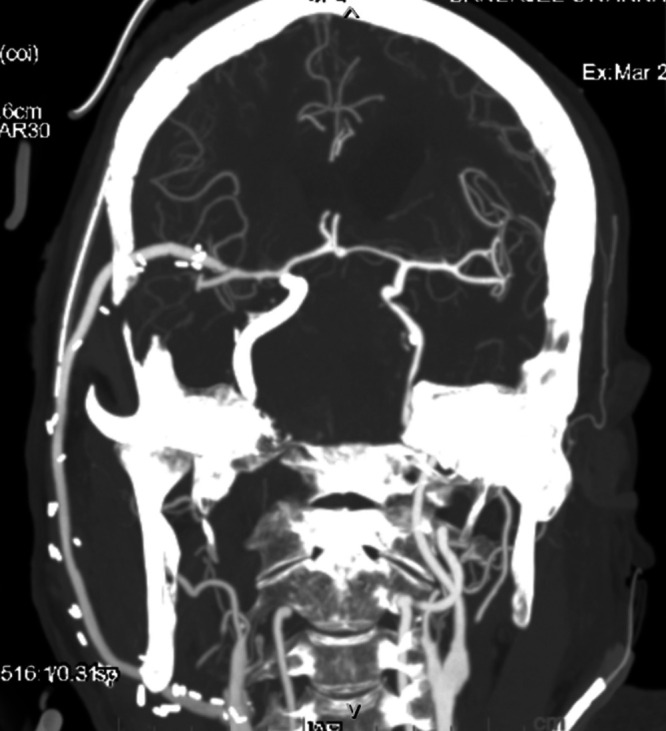

FIG. 5.

Postoperative three-dimensional reconstructed CT angiography of the head and neck vessels confirming patency of the external carotid artery–M2 segment of middle cerebral artery bypass graft.